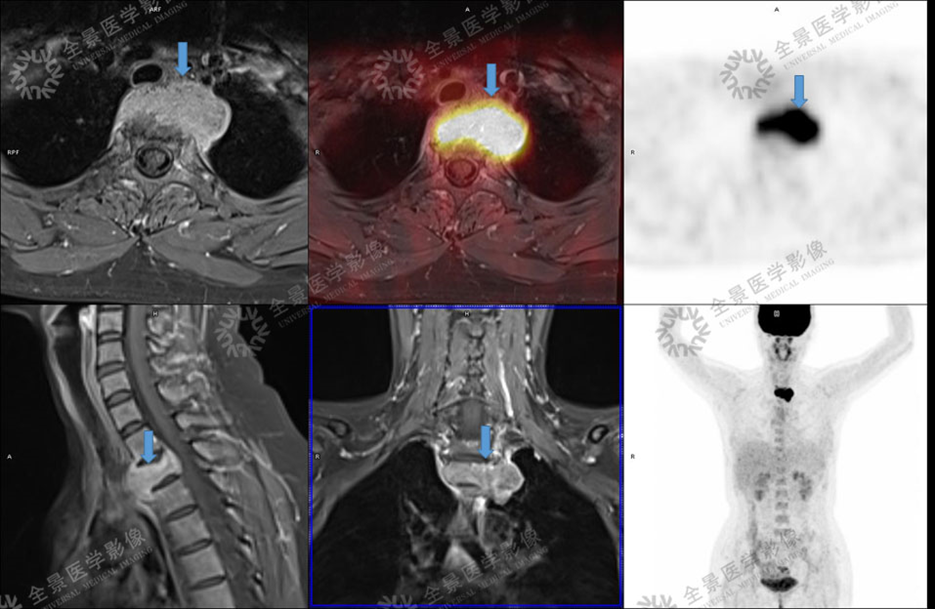

骨关节

案例 :骨巨细胞瘤

T2WI不均匀等信号,

PET/CT显示:T3骨质破坏并周围软组织肿块形成,FDG明显摄取增高。

增强扫描明显强化